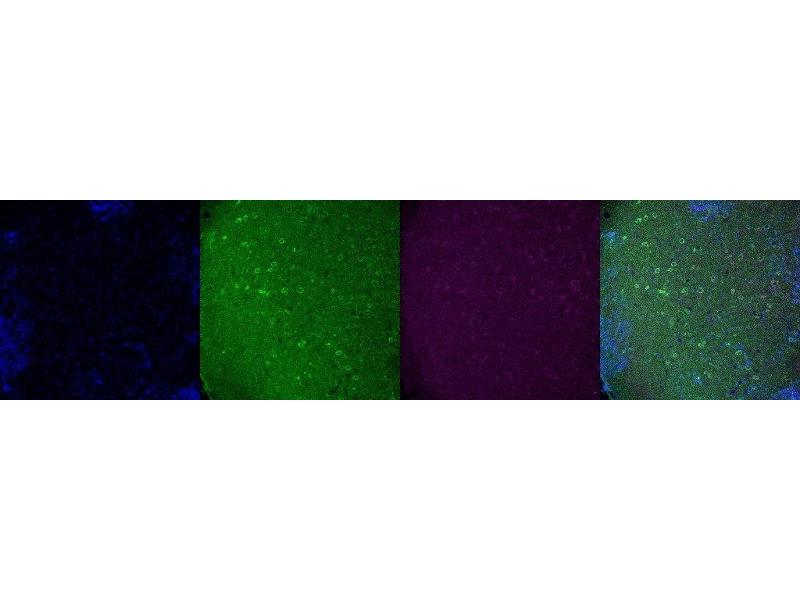

Tryptophan Hydroxylase 2 抗体

The 小鼠 单克隆 anti-Tryptophan Hydroxylase 2 antibody is suitable to detect Tryptophan Hydroxylase 2 in samples from 人 和 小鼠. It has been validated for IHC.

Immunohistochemistry (IHC)